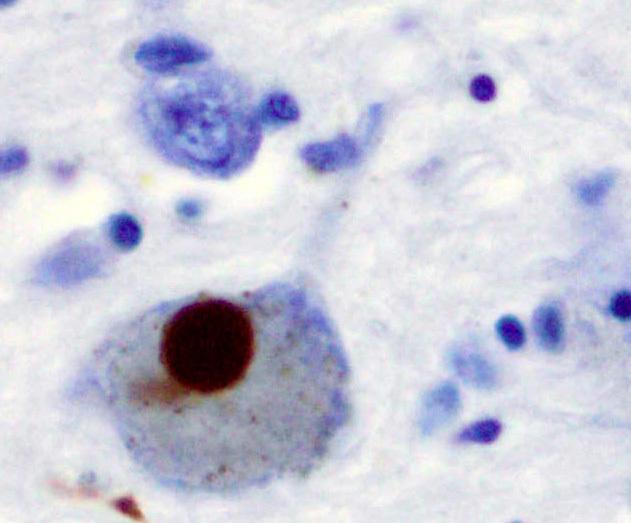

Тельца Леви, окрашенные по альфа-синуклеину

Нейродегенеративные заболевания, такие как болезнь Паркинсона, Альцгеймера и прионные инфекции, во многом связаны с накоплением в мозге неправильно свернутых белков, образующих токсичные амилоидные агрегаты. Особый интерес для науки представляет взаимодействие между разными классами таких белков, например, прионного белка (PrP) и альфа-синуклеина (α-syn), ключевого игрока в развитии болезни Паркинсона. Однако данных о таких взаимодействиях накоплено недостаточно, и они зачастую противоречивы.

Еще более интригующим оказалось влияние прионного белка на альфа-синуклеин. Ученые обнаружили, что полноразмерный PrP, его N-концевой фрагмент и даже зрелые фибриллы PrP резко ускоряют агрегацию как нормального альфа-синуклеина, так и его мутантной формы A53T, связанной с ранним развитием паркинсонизма. Однако ускорение не приводило к образованию типичных длинных структурированных фибрилл. Вместо этого формировались отдельные разнородные агрегаты.